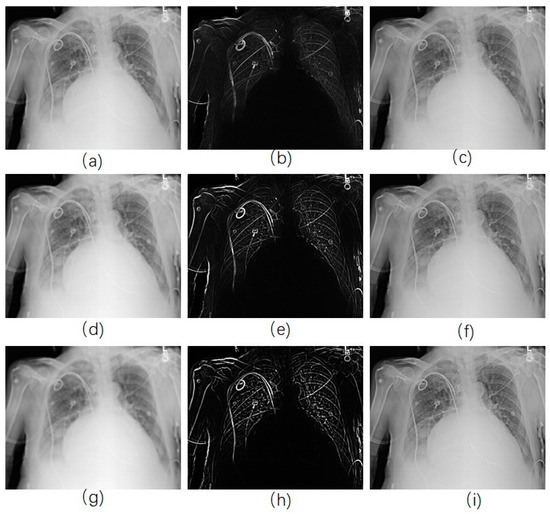

For traditional USM method, we have chosen different kernel size for Gaussian filter ( 15 × 15 , 19 × 19 , and 23 × 23 separately). Figure 3 shows a CXR from the portable CXRs database. The contrast of line structure in the spine and heart area is limited, and it is hard to find the tips of ET and NT. Enhancement is necessary for ICU CXR. Figure 4 shows the enhanced results obtained by using traditional USM. The EMEE value for the original image was 0.491. After enhancement, the EMEE values were improved to 0.841 (Figure 4c), 0.980 (Figure 4f), and 1.106 (Figure 4i), corresponding to the Gaussian kernel size of 15 × 15 , 19 × 19 , and 23 × 23 , respectively. Although, the EMEE values were improved, some important edge information still did not show clearly in the image, especially when the kernel size was smaller. When the kernel size of Gaussian increased, the noise and the edges were enhanced simultaneously. As a result, Figure 4c,f,i did not have high contrast, which was predictable based on the properties of the traditional USM algorithm.

Figure 4. CXR enhancement by use of traditional USM model. (a,d,g) were the smoothed images by use of 15 × 15 , 19 × 19 , 23 × 23 Gaussian kernel, respectively; (b,e,h) were the corresponding Unsharp masks to (a,d,g); (c,f,i) were the corresponding enhanced images.